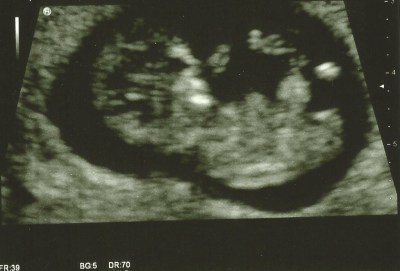

I was called in for my scan on time (what’s going on, that never happens, like ever!) and was told it was going to be conducted by a trainee. ‘Oh great’ I thought. My last scan on my little girl was conducted by a trainee and she died a few days later. I’m not saying there’s a link, but maybe they pressed too hard, or didn’t pick up on something they should have? I will never know. Anyway this lady asked me to sit on the bed while they looked through my notes, they openly discussed them until the senior sonographer called the trainee over to the corner and pointed at a bit of my notes and I heard her whisper late term and then something about sensitive. I can only assume they had got to the part of the notes that told them about my miscarriage early last year. This bugged me, why did she need to whisper as if to keep me out, I do know about it, it happened to me! The trainee came back, lay me down, put the jelly on and proceeded with the scan. Initially as the baby came in to view on the screen all I could see was the shape, I stared and stared trying to see some heart movement, which the trainee quickly told me ‘so there’s baby with a nice heartbeat’ relief washed over me from my moment of panic and a few seconds later Shrimp had thrown their hand above their head as if to wave hello! There was a lot of wiggling of arms and legs, and hiccuping, until they tried to get the length measurement at which point shrimp rolled on their side and fell asleep. Fantastic! They tried every which way to position the scanner so they could measure the length, but eventually asked me to roll on my side, and then back onto my back to see if this had shifted baby’s position! I did offer to stand up and jump around, they didn’t take me up on it, though I’m pretty sure it would have been easier if they had. After three more ‘just roll on your side’ they decided they had the best angle they were going to get and proceeded with the measurements. Shrimp was 66.3mm head to rump which they said put me at 13 weeks (5days more than they told me I was at the 8 week scan) and that this made my due date 8th August. After requesting a couple of pictures we went back to the waiting room to wait to see the consultant.

Having my blood taken was the most relaxing part of my morning, and that’s saying something! I had a lovely conversation with the lady and, following normal routine, I looked solidly at everything else but the needle stuck in my arm. After this we headed back to the ultrasound reception hopeful, if nothing else they’d have been able to photocopy the one they had, however the lady who had done my scan had only just come out and they went to see what they could do. I was sent off to wait, yet again and about 5 minutes later was called back and given a second picture which I was told unfortunately the only one they had saved was the one with the measuring line on, though she assured me you could hardly see it… (I disagree) Thankfully the receptionist was lovely and gave us one of the tokens back to use next time, hopefully we don’t lose it before then!!